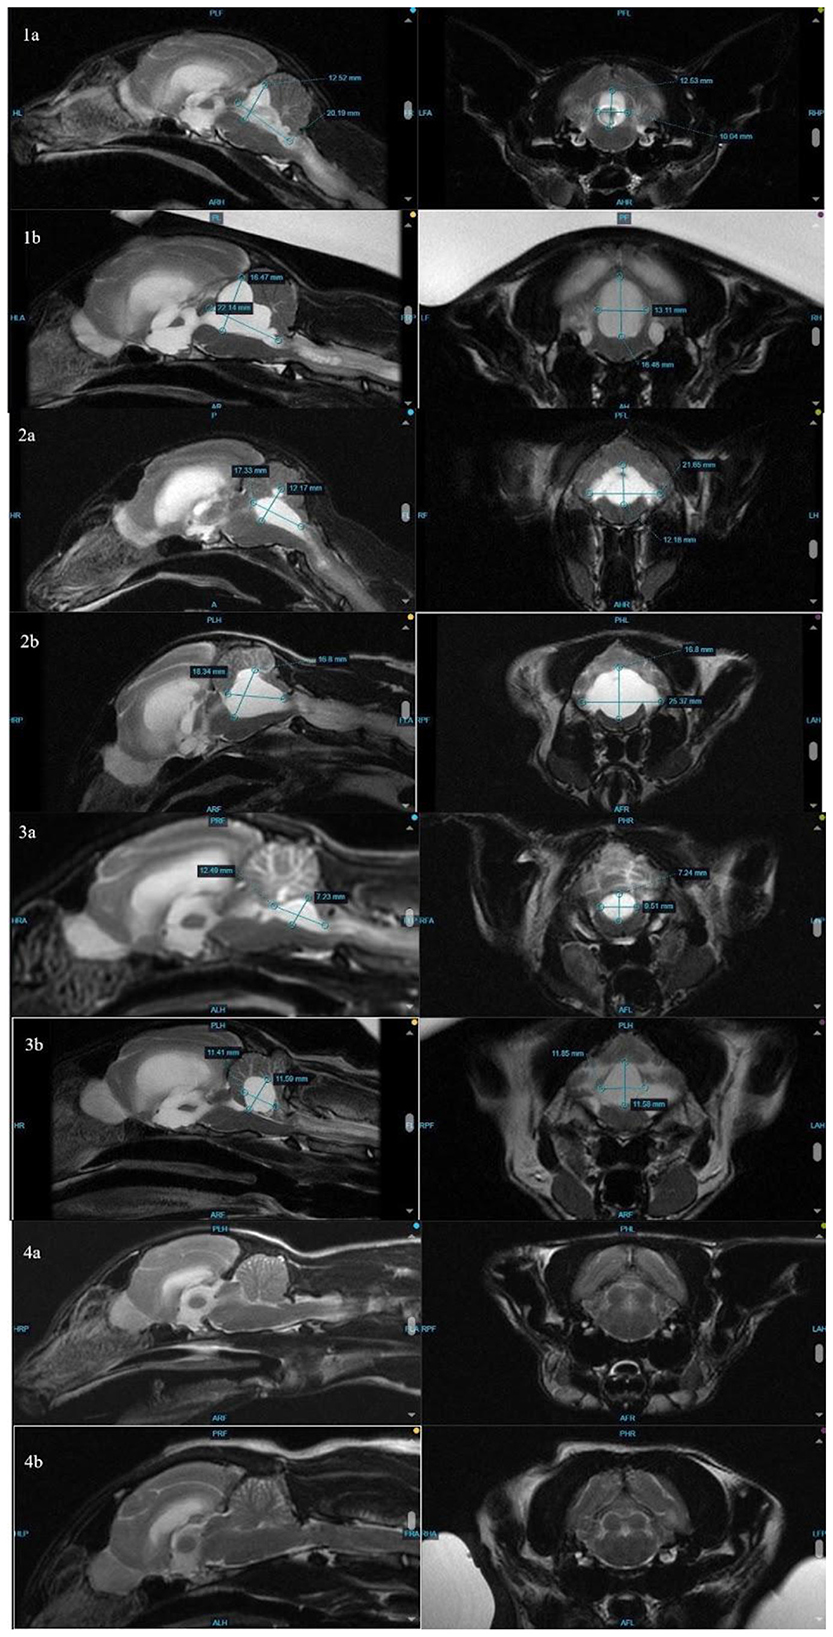

The distribution of fluid in the ventricles, with the disproportionate enlargement of the fourth ventricle, would explain clinical signs of vestibular dysfunction seen in these cases due to compression of the cerebellum and brainstem. While lateral ventricle size and its relation to brain height has been studied to evaluate clinical hydrocephalus in cats, there is a paucity of veterinary literature classifying fourth ventricular size, especially in cats (14). In dogs, although the size of the fourth ventricle is found to be statistically different between hydrocephalus and ventriculomegaly groups, it is suggested that body mass may affect size of the fourth ventricle (24). Individually, each affected cat in this series presented with increased size in all ventricles, including, most dramatically, the fourth ventricle. In contrast, Case 4 showed no discernible enlargement of the fourth ventricle pre- or post-treatment (Figure 2). While there is no standardized ratio or measurement that has been proven to characterize the size or volume of the fourth ventricle in cats, in all affected cats, the fourth ventricle displays progressive dilation.

Figure 2

MRI images showing sagittal and transverse cross-sections of an animal’s brain and skull. Panels 1a to 4b display different sections with various measurements indicated by lines and annotations. Each panel shows differences in cross-sectional anatomical features for comparison. Measurements in millimeters are visible in each image.

Figure 2. Comparison of measurements (height, width, and length) of the fourth ventricle at initial MRI (1–4a) and repeat MRI (1–4b). Note that the fourth ventricle in cat 4 (clinically normal at time of follow-up MRI) is too small to measure.